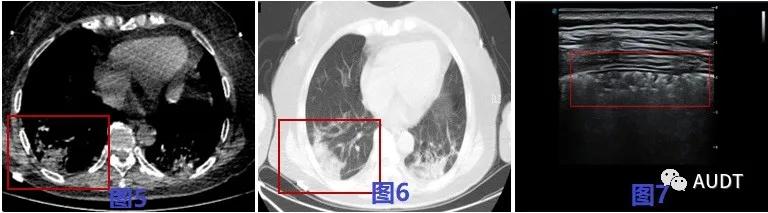

进展后期,图8-9 CT扫描显示双肺呈大片样,条带样实变影,图10-12超声显示相应肺周胸膜局限性增厚。实变病灶内超声可见粗大支气管充气征,伴病灶后弥漫性B线,实变区域实变与正常肺组织交界区可见少量星点状血流信号。